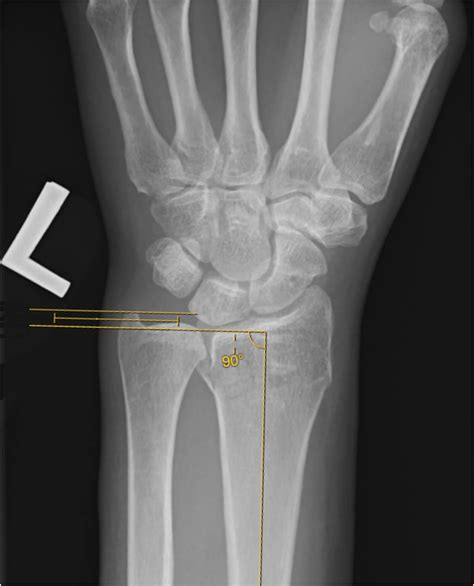

Diagnosing an Ulnar Styloid Fracture

Diagnosing an ulnar styloid fracture typically involves a combination of physical examination and imaging tests. The diagnostic process may include:

• Physical Examination: A healthcare provider will assess the wrist for pain, swelling, and deformity. They may also check the range of motion and stability of the wrist.

• X-rays: These are the primary imaging tool used to confirm the diagnosis. X-rays can show the location and extent of the fracture.

• CT Scan: In some cases, a CT scan may be ordered to provide a more detailed view of the fracture, especially if surgery is being considered.